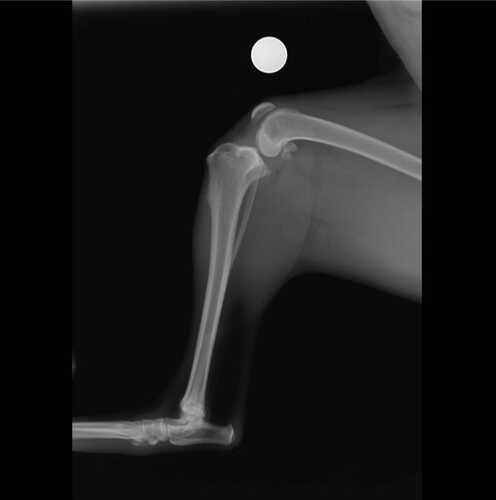

A Cindy tem 1 ano e 8 meses, é muito brincalhona e agitada. Sua brincadeira favorita é correr e pular alto. Um certo dia em uma de suas brincadeiras, a Cindy pulou e escorregou, o que acabou levando a uma ruptura do ligamento cruzado, fazendo ela ter dor e apoiar a pata no chão com dificuldade.